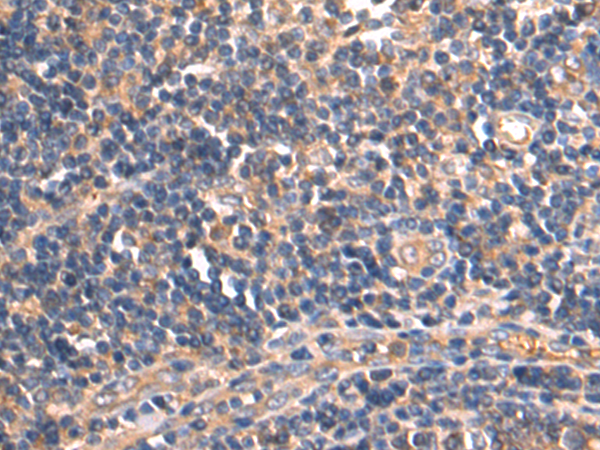

分类: 科研抗体货号: P09849别名: SRCRB4D; S4D-SRCRB; SRCRB-S4D应用: IHC反应种属: Human